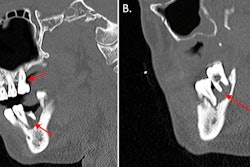

At the hospital, the child underwent a CT scan, which revealed that his orthodontic wire had migrated into his left temporal lobe. He was then given vancomycin and midazolam and intubated. The child underwent an x-ray, which confirmed the wire entering his skull, the authors wrote.

Due to a high risk of infection, he was started on metronidazole and ceftriaxone. He was also sedated with propofol and fentanyl and underwent a CT head and neck angiography. Imaging confirmed the wire entered the child’s skull via the foramen ovale and ending up in the temporal lobe. A 2.4 × 1.6 cm intraparenchymal hemorrhage was associated with the wire. The hemorrhage showed early signs of brain swelling due to leaking blood vessels, the authors wrote.

Additionally, imaging confirmed that other major vessels within the area were spared. The wire was successfully removed, the authors wrote.